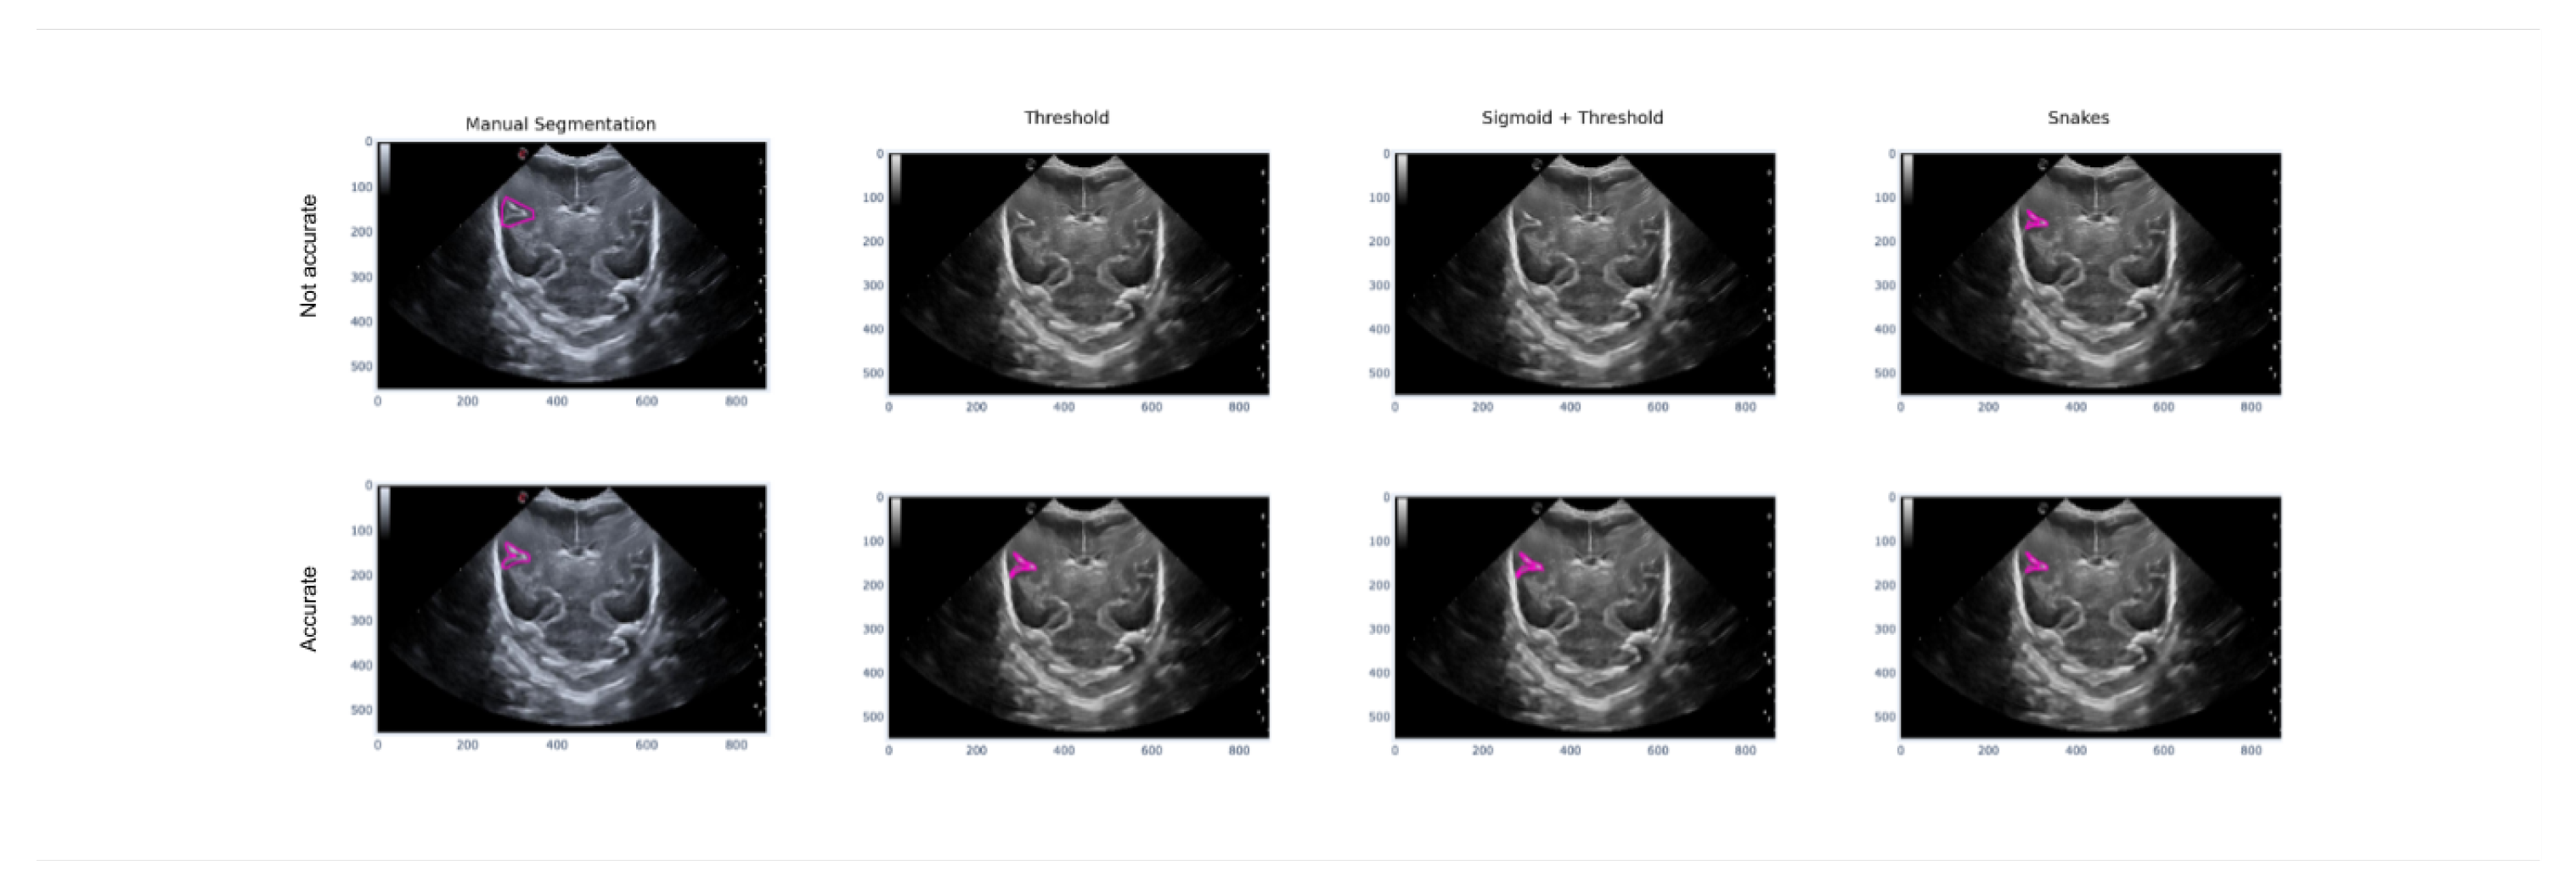

Three different cases will be analyzed. Firstly, the behavior of the algorithms will be observed in different grooves shown in the image. Secondly, an analysis will be carried out on the Sylvian groove to observe how it behaves according to the noise that appears in the image. Lastly, each method’s behavior will be analyzed according to how the manual segmentation has been done.

To conclude this section and proceed to the conclusions, the third case is explained, which demonstrates how each method performs segmentation depending on the precision of the manual segmentation. Figure 18 illustrates how imprecise manual segmentation, which defines the area of the image where the groove is located, renders the Threshold and Sigmoid + Threshold methods ineffective. However, if the manual segmentation is more precise and follows the shape of the groove, these methods provide satisfactory results. The Snake method, on the other hand, is observed to be unaffected by the way in which segmentation is performed, and it provides satisfactory results in both cases of precise and imprecise manual segmentation.

Figure 18. Example of how the segmentation results vary with different methods depending on the accuracy of the manual segmentation, with the first row showing more precise manual segmentation and the second row showing less precise manual segmentation.